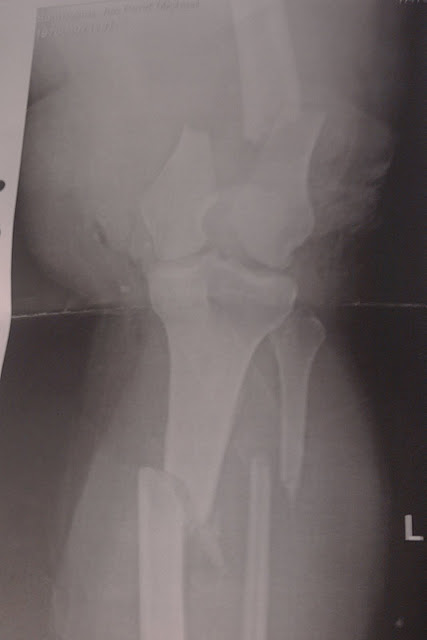

Mulla nilkka samannäköinen sisältä kuin ketjun aloittajan kuvassa, sillä erotuksella että reikänauhaa on nivelen molemmilla puolilla ja pari pidempääkin ruuvia. (moottoripyöräily)